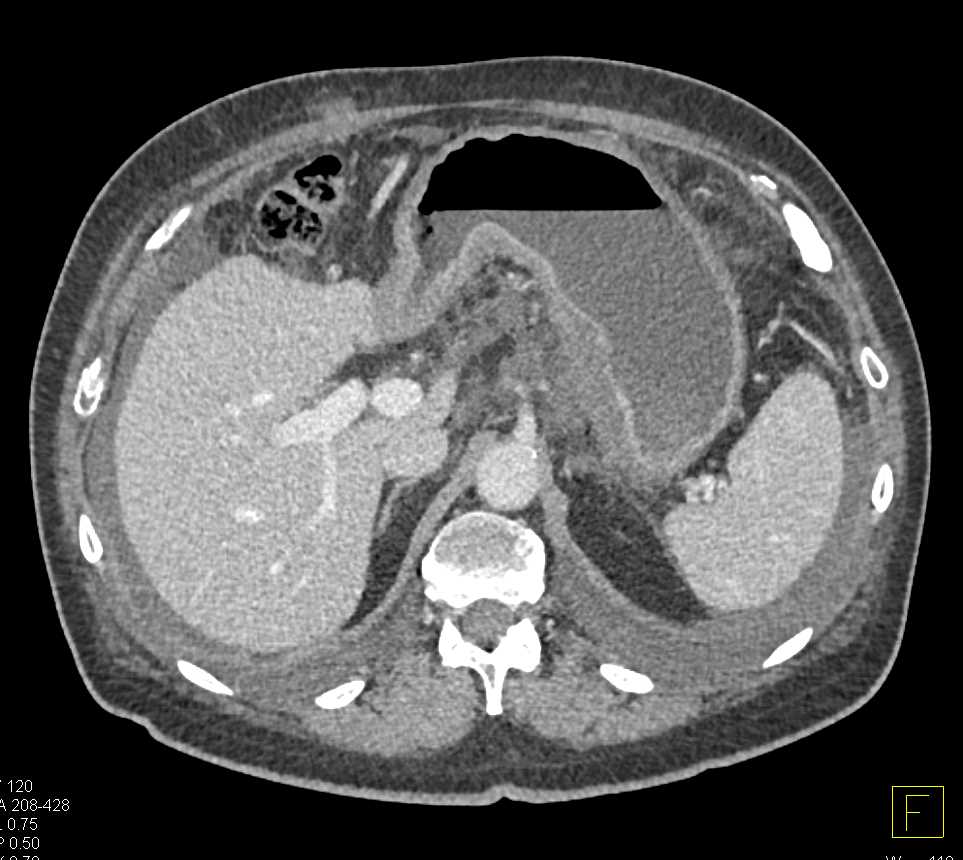

Lagre Gastric GIST Tumor